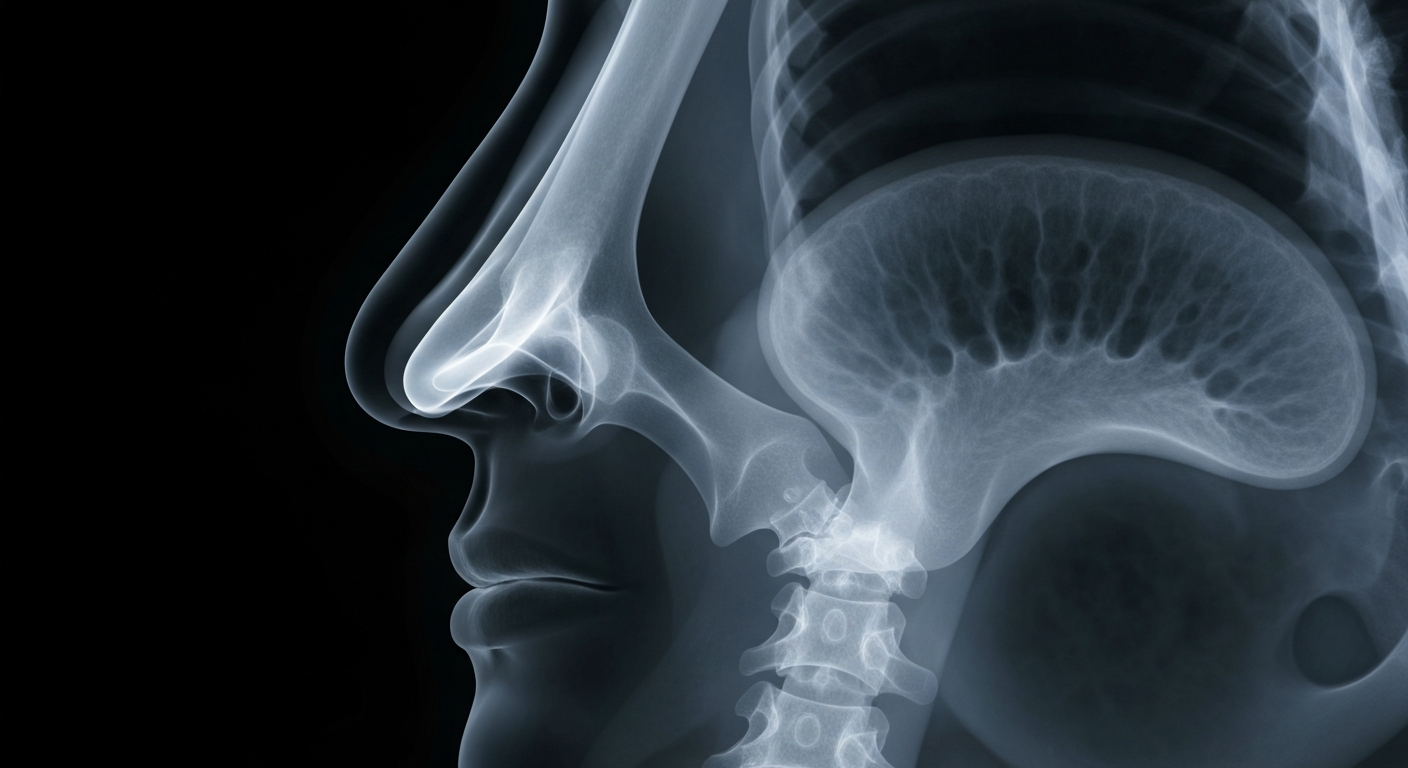

As seasonal allergies and common colds share many overlapping respiratory symptoms, an X-ray view of the nasal passages reveals the challenge in determining the underlying cause.Cornell TodayAs temperatures warm and pollen levels increase across the Midwest, many people are experiencing sniffles, sneezes, and other respiratory symptoms - leaving them wondering whether they have a cold or seasonal allergies. While colds and allergies share similar symptoms, there are some key differences that can help people determine the cause of their discomfort.